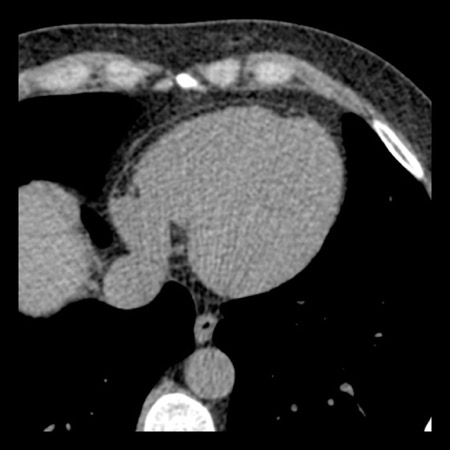

case 4 – CAD-RADS 3/P1/I+ thrombus left ventricle

First, scroll through the CTA images.

How would you describe the findings on the coronary CTA?

The findings are:

- Moderate (50-69%)

stenosis in the proximal LAD caused by a non-calcified plaque. - Variant of

sinoatrial (SA) nodal artery. The artery usually arises from the RCA as a second

branch after the conus artery, however in this case it arises from the LCX,

courses behind the aorta, anastomosing with the right atrium and with a small

branch supplies the SA-node of the heart. - Thrombus in the

apex of the left ventricle. - CTP was performed

in this patient. CTP showed a perfusion defect at stress imaging in the

territory of the LAD (I+), at rest no perfusion defect was visible.

This patient classifies as CAD-RADS 3/P1/I+, which means

this patient requires further investigation.